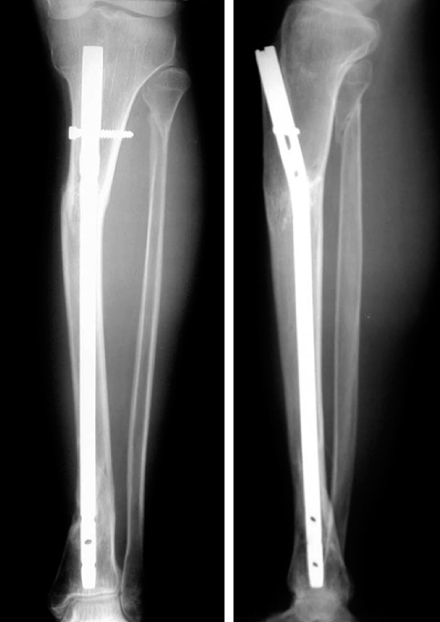

Fig. 9

(A, B) Initial radiographs show the segmental fracture of the proximal and distal tibial shafts.

(C, D) The proximal fracture was reduced and stabilized with a 1/3 tubular plate through a small incision before locked tibial nailing to prevent malalignment. Postoperative radiographs show anatomical alignment of the fracture fixed with a locked nail and a small plate.

(E, F) Radiographs 7 months after surgery show the healed fracture with external callus in good alignment.

Fig. 9 (A, B) Initial radiographs show the segmental fracture of the proximal and distal tibial shafts. (C, D) The proximal fracture was reduced and stabilized with a 1/3 tubular plate through a small incision before locked tibial nailing to prevent malalignment. Postoperative radiographs show anatomical alignment of the fracture fixed with a locked nail and a small plate. (E, F) Radiographs 7 months after surgery show the healed fracture with external callus in good alignment.